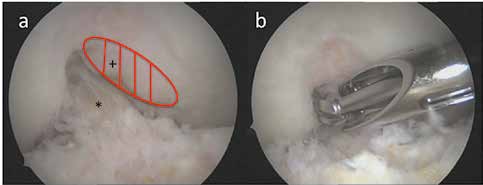

Intraartikuläre symptomatische Veränderungen können arthroskopisch therapiert werden, besonders, sofern mechanische Ursachen für die Beschwerden verantwortlich sind 11 12. Osteophyten sind eine typische Veränderung bei Arthrosen. Es sind knöcherne Sporne, die mit Faserknorpel überzogen sind und häufig am Rand der Gelenkknorpelzone infolge einer periostalen Reaktion entstehen. Auch ohne Knorpelschäden können sich mit zunehmendem Alter Osteophyten bilden und die Ursache für Schmerzen und Funktionsstörungen darstellen. Sie können zu einem Impingement – insbesondere im Bereich der Kollateralligamente und der interkondylären Notch – führen. Am Patella-Rand erzeugen Osteophyten manchmal sichtbare Schleifspuren im korrespondierenden Trochlea-Knorpel. Abgebrochene Osteophyten können sich zu freien Gelenkkörpern entwickeln. Eine Stenose der interkondylären Notch kann zu einer mukoiden Hypertrophie des vorderen Kreuzbandes mit Streckhemmung und sekundärer Instabilität führen. Die arthroskopische Entfernung von Osteophyten und die Notch-Erweiterung haben sich daher in der Arthrosebehandlung mit signifikanter Schmerzreduktion und Extensionsverbesserung bewährt (Abb. 2).